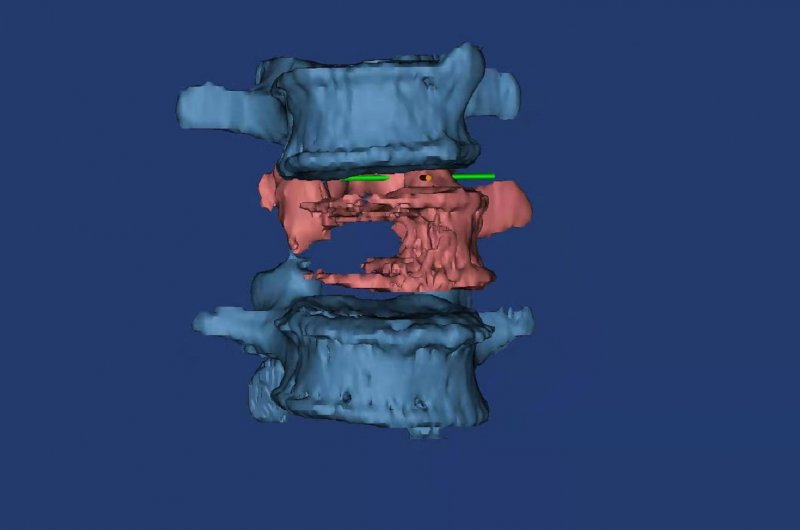

术前3D打印模型显示腰3椎体右侧半被肿瘤“吃”空了。

术前3D打印规划术中人工椎体大小形态。